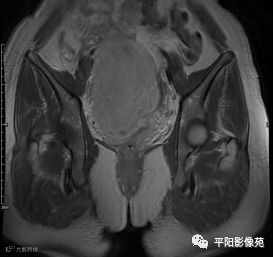

(宫腔内见金属节育环伪影)宫颈区见不规则形等T1稍长T2信号软组织肿块,DWI序列呈明显高信号,大小约为3.87cmX2.64cm,双侧宫颈基质低信号环连续性中断,病灶向子宫右后上方生长,周围脂肪间隙模糊,增强扫描明显强化,强化程度低于子宫及宫颈实质;子宫后方、子宫直肠间隙见不规则形长T1长T2信号软组织肿块,DWI序列呈高信号,大小约10.12cmX4.82cmX10.29cm,病灶呈分叶状,向下方生长与宫颈分界不清,与直肠分界尚清,增强扫描明显不均匀强化。

1.宫颈癌(T1b1N0Mx)

2.子宫后方、子宫直肠间隙占位,考虑来源于间叶组织肿瘤可能性大